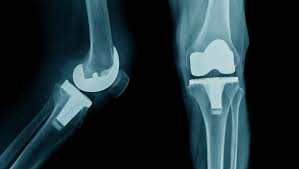

Total knee replacement is a surgical procedure that removes damaged cartilage and bone from the knee joint. Then surgeons replace them with artificial components, or implants, to recreate smooth, pain-free knee motion. This surgery offers predictable pain relief and restored walking ability.

At Varunam Super Speciality Hospital, total knee replacement follows a structured approach. Preoperative imaging and consultations help Dr. Utsav Agrawal plan each surgery precisely. This planning includes implant selection, bone alignment, and surgical technique.

During surgery, the damaged joint surfaces are removed with care. The new implants restore joint mechanics and reduce friction. The operating theater uses advanced equipment to ensure safety and accuracy. After surgery, patients receive attentive monitoring, pain control, and early mobilization support.